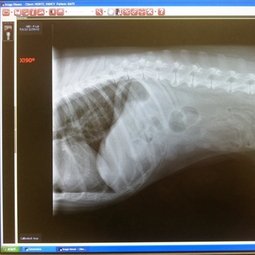

- Digital Radiology / X-Ray

Digital x-rays are beneficial to you, your pet and our hospital in many ways! First, digital x-rays allow our doctors to better diagnose your pet. They are more clear and detailed. Our doctors can also have a better view of your pet's organs and skeletal system because digital images can be enhanced. For example, if your pet is experiencing back problems, the doctor can zoom in on specific areas of your pet's back and see very small details that would not have been visible on traditional x-rays. Digital radiography also allows us to be more efficient. It is time-saving. Our technicians can take the x-rays in our DHEC approved x-ray room and within minutes, the x-rays are available for your pet's doctor to review on any computer in our hospital. The doctor will then review the x-rays with you in the exam room on the large computer screens. Conveniently, digital images can also easily be emailed to you or other veterinarians if requested! Digital x-ray also saves energy. We also appreciate not having to deal with the chemicals associated with developing traditional x-rays. All-in-all, digital x-rays are incredible and we are so happy to have them available for our patients!